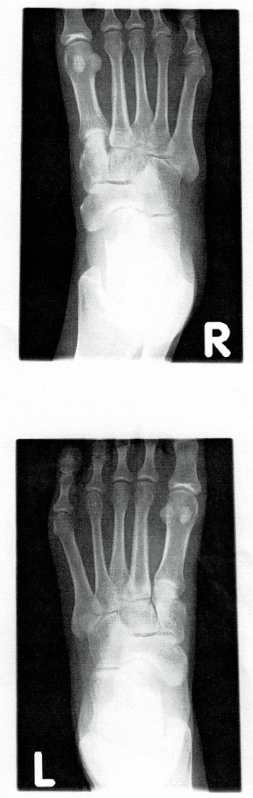

三方向撮影のうちの、一方向だけ掲載。

このレントゲン画像は、ディスプレイに表示されたデータをスクリーンショット→プリントアウト

それを家庭用プリンターで600dpiでスキャンしたから、鮮明じゃないです。

何の異常もない、疲労骨折もないレントゲン写真。

異常ないから、足はちゃんと保持して、様子を見るしかないですね、と。

疲労骨折ではないという確証と、レントゲンが収穫でした。

初めて手に入れた足の骨のレントゲンです。

「足の骨ってこんなたくさんあるんやな」

そのうち足の骨は左右で56個。種子骨含む。

数でいくと1/4の骨が足です。